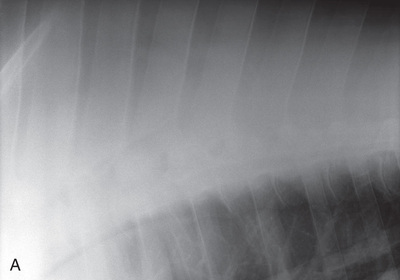

| Thorax | Lateral (Fig. 24.60) | Affected side | Horizontal beam on opposite side. | See comments later for specifics: | Patient standing. Portable unit not powerful enough. |

| Abdomen | Lateral (Fig. 24.61) | On side (most lesions on midline). | Opposite side. | Last rib for small horses: | Multiple laterals required for larger patients. |